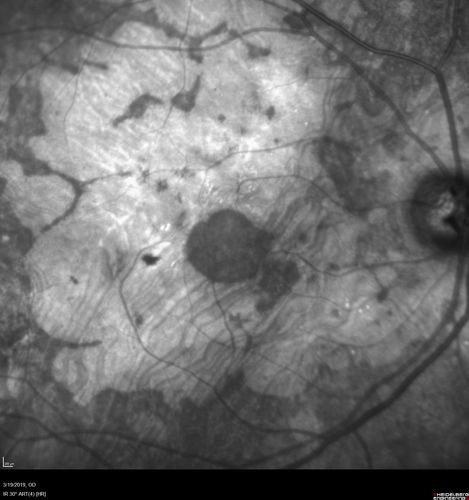

Concentric Geographic Atrophy

76 year old man Gradual vision loss

20/32 OD; 20/40 OS

No medicines, Non-smoker

Working and Driving